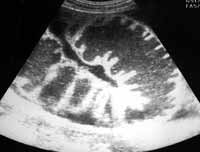

Определение висцеро-париетальных сращений в брюшной полости базировалось на наличии фиксированных к передней брюшной стенке петель кишки, не смещаемых относительно ее при активных дыхательных движениях, а также на резких перепадах диаметра кишечных петель (13). При спаечной непроходимости в положении больного на боку обнаруживалась фиксация петель тонкой кишки и их сращение между собой. Более того, тщательный осмотр петель кишки позволил выявить перепад диаметров кишки, а также место сдавления расширенными петлями спавшегося «клубка» и, в результате, более точно констатировать наличие уровня обтурационной непроходимости (Рис. 3). Кроме того, непосредственно у места обструкции антиперистальтика была снижена или отсутствовала, а стенки кишки были значительно толще, чем в проксимальных отделах. Однако растянутые петли тонкой кишки могли закрывать место обструкции (6).

[Увеличить]

Рис. 3. Эхограмма того же больного. Расширенные петли тонкой кишки сдавливают спавшиеся петли подвздошной кишки, расположенные дистальнее места обструкции.